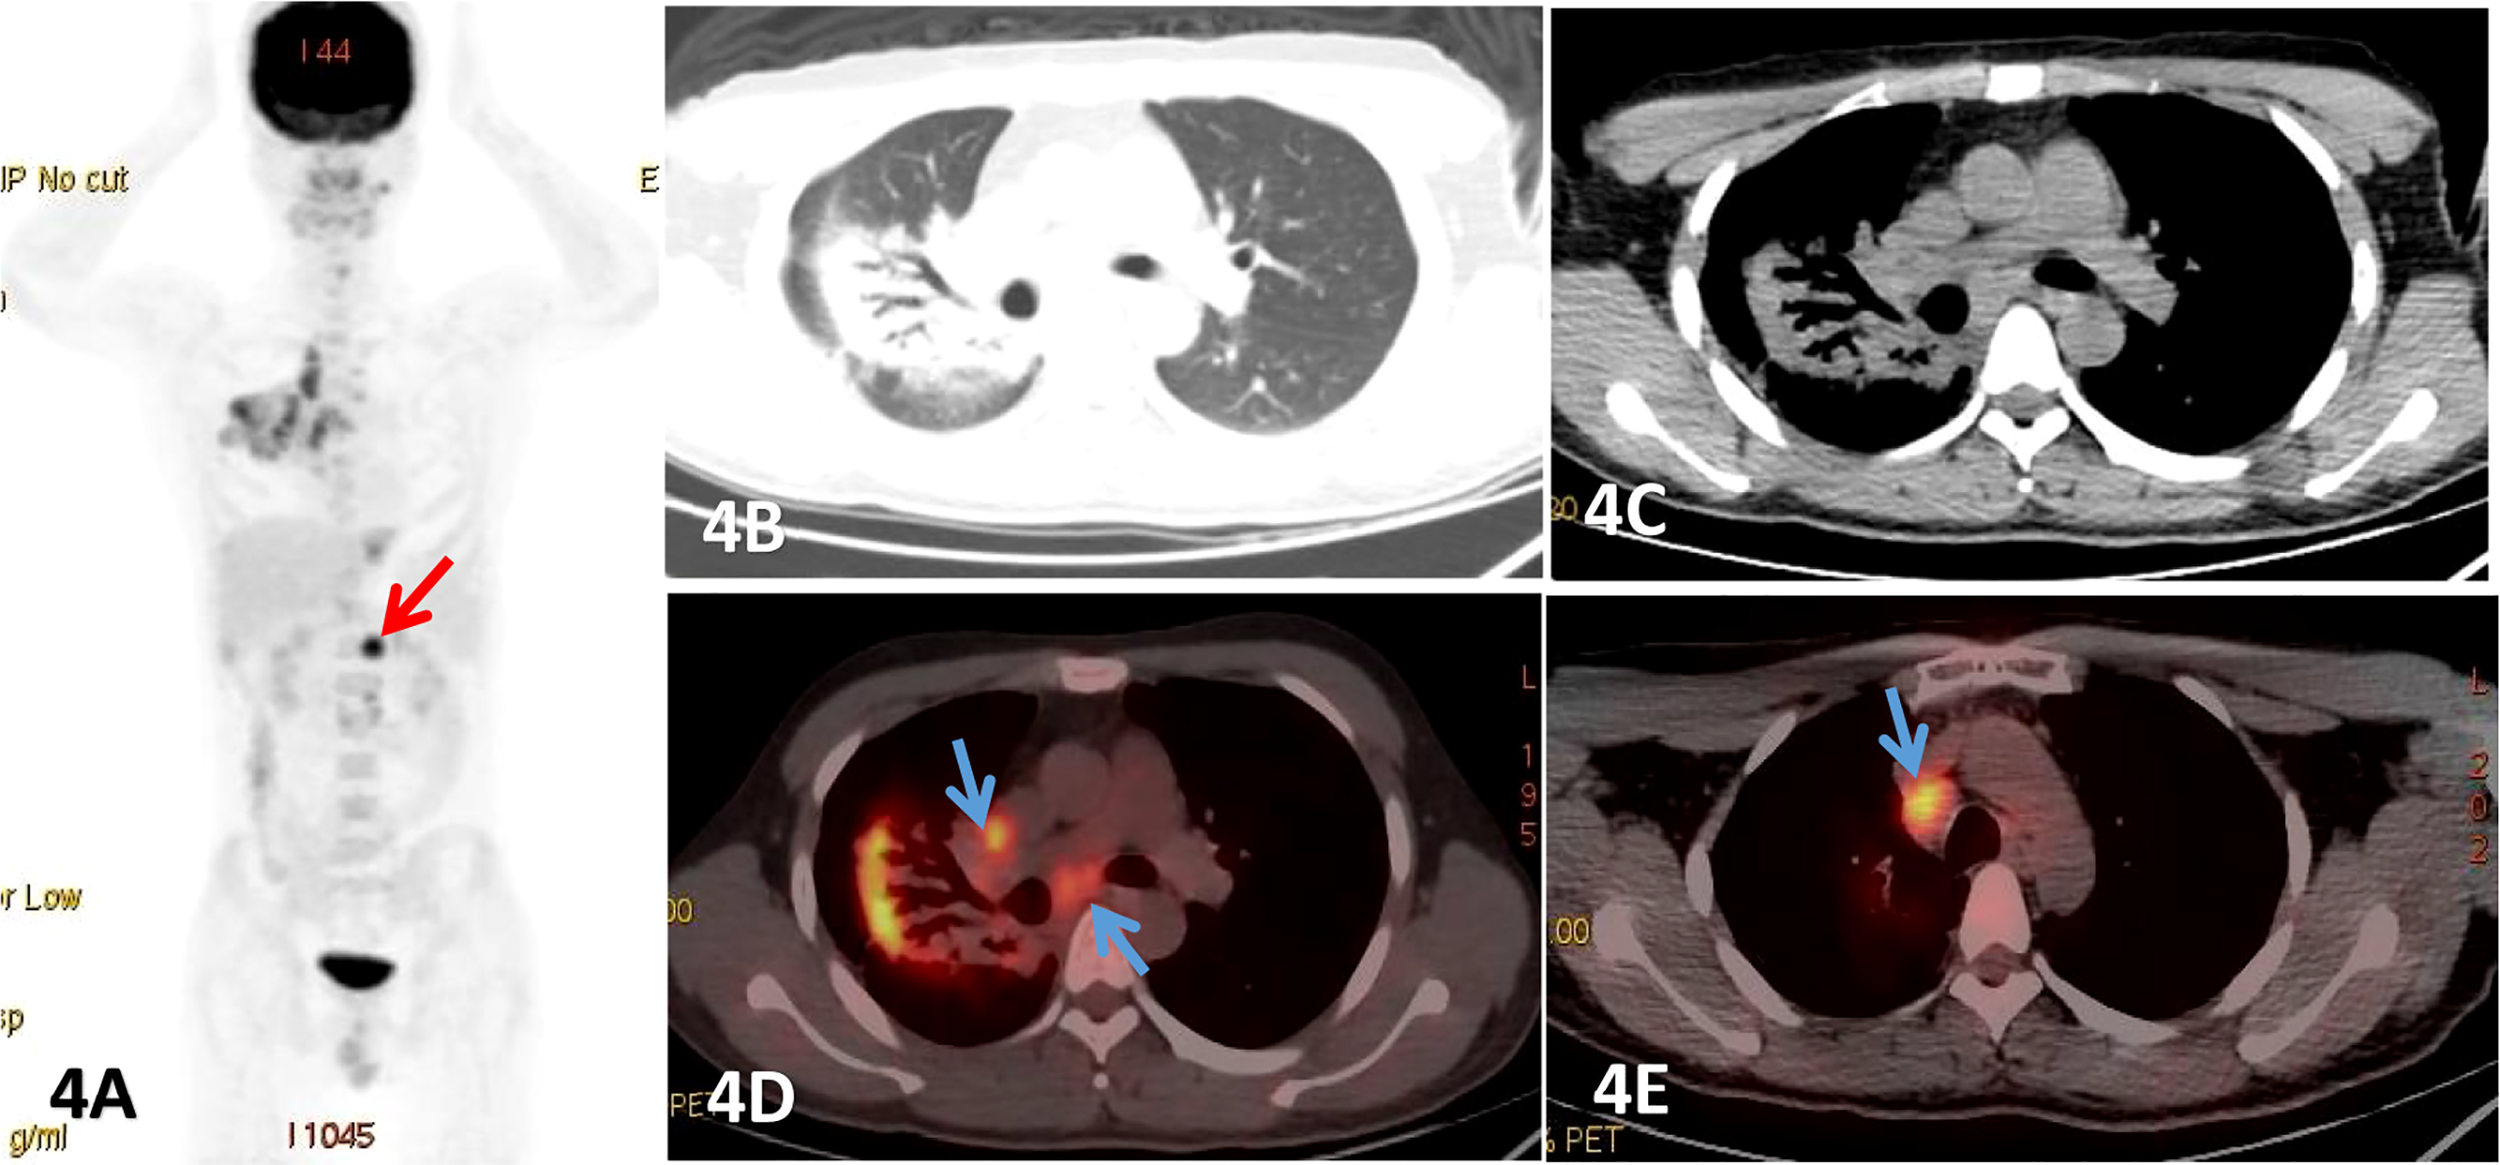

In our study, all the 19 patients showed increased metabolism, but the uptake degree was not consistent. The SUVmax of lesion ranged from 2.58 to 22.6. The FDG uptake of DLBCL was significantly higher than that of MALT lymphoma (P<0.001). But the FDG uptakes in MALT lymphomas and T-cell lymphomas were quite similar. We also found that the FDG uptake of nodular/mass lesions was higher compared to pneumonia consolidation, while the FDG uptake of clinical I stage PPL was found to be lower than that of other stages, with statistically significant differences (P<0.05). One study reported no significant differences between positive and negative 18F-FDG PET/CT when comparing the metabolic and morphological pattern of presentation, presence of bronchiectasis and air bronchogram (35), which is consistent with our results. In addition, a very important feature of 18F-FDG PET/CT is that whole-body imaging is possible with a single scan and comprehensive information can be obtained, which is conducive to the detection of extrapulmonary lesions and plays an important role in the staging of PPL. Moreover, the different stages have different treatment methods, for example, IE˜II1E PPL is mainly treated with surgery (25). In the current study, one patient was found to have subphrenic lymph nodes with high metabolism, which raised the stage from IE to III (Figure 4). In the other 2 mediastinal lymph nodes, although their diameter was less than 10-mm, but 18F-FDG PET/CT metabolism was significantly increased with a SUVmax of 6.2. In addition, the postoperative pathology confirmed the infiltration that also changed the stage from IE to IIE. Furthermore, 18F-FDG PET/CT has been shown to be considerably more accurate than anatomical imaging in assessing response, as it is able to distinguish between viable tumor and nonviable post treatment findings and can identify individuals with treatment resistance to certain forms of chemotherapy at an early stage, providing the clinicians with a sufficient time window to modify the therapeutic strategy (40, 41).

Figure 4

Male, 25 years old, fever, cough, dyspnea for more than 2 months, (A) was PET MIP image, (B, C) were lung and mediastinum CT transection scan, (D, E) were PET/CT fusion image of mediastinum.Patchy consolidation shadows were observed beside the right hilar, and obvious dilated bronchial shadows were observed in the lesions, presenting a translobular distribution with clear margins, which FDG uptake increased with a SUVmax of 8.52, and lung MALT lymphoma was detected by fiberbronchoscopy biopsy. And an enlarged lymph node with significant uptake of FDG was also seen below the diaphragm (red arrow). Endoscopic ultrasonic-guided transbronchial needle aspiration.